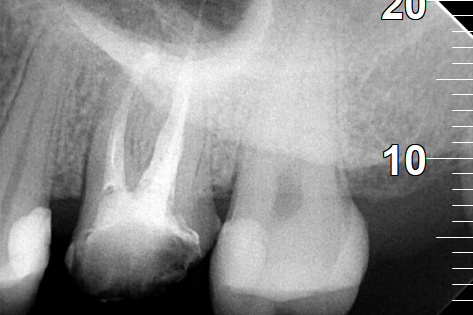

Ο ασθενής πονούσε πολύ στον άνω γομφίο, που είχε απονευρωθεί πριν από χρόνια. Αποφασίστηκε η επανάληψη απονεύρωσης του δοντιού, κατά την οποία διαπιστώθηκε οτι υπήρχε και τέταρτος ριζικός σωλήνας που δεν είχε βρεθεί και επεξεργαστεί κατά την πρώτη προσπάθεια απονεύρωσης. Πλέον το δόντι είναι ασυμπτωματικό.

Παλιά απονεύρωση του δύο άνω γομφίου

Νέα απονεύρωση στον άνω γομφίο